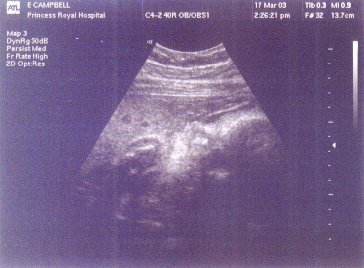

I have now put my newer scan pics, from the 17th of March, up here as you can see to the left. Because they were done at 32 weeks the baby is really big now and all you can fit into the scan is its head and hand. It looks like it could be sucking its thumb.